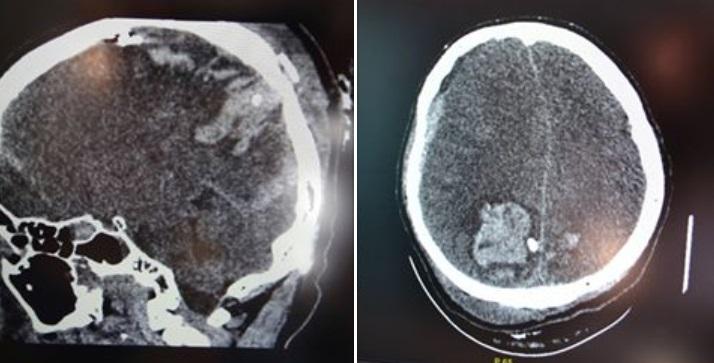

«Микола, старший сержант, 48 років із Кіровоградської області. Донька - Ярослава, санінструктор тієї ж частини. Раптовий артобстріл не залишав шансів. Міна вибухнула за три метри від них. Микола своїм тілом накрив доньку», - написав Риженко.

За його словами, поранених доставили до лікарні 25 травня. Боєць отримав тяжке осколкове поранення голови й переніс безліч операцій у лікарні.

«Сьогодні вночі всі кращі реаніматологи Мечникова на чолі з Ігорем Йовенком чотири рази запускали його серце», - розповів головний лікар.